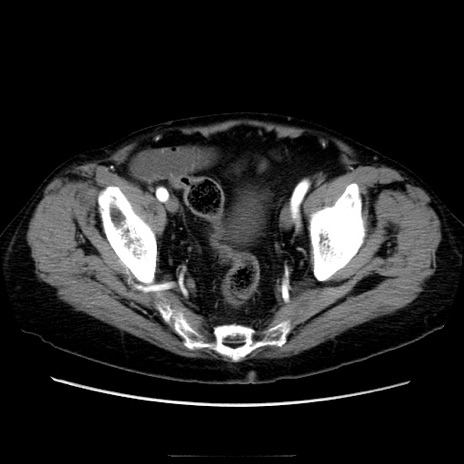

症例21(横断像)

【症例】70歳代男性

【主訴】腹痛

【現病歴】肝硬変・肝細胞癌にてかかりつけの方。約9時間前に食後より腹痛出現。症状が徐々に増悪し、嘔吐出現したため来院。

【既往歴】肝硬変、肝細胞癌(RFA、TACE後)

【身体所見】意識清明、表情苦悶様、BT 36℃、BP 129/78mmHg、P 88bpm、SpO2 97%(RA)、右上腹部から心窩部にかけて圧痛あり、反跳痛なし、筋性防御あり。

【データ】WBC 5800、CRP 0.16